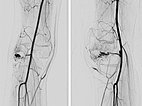

After successful embolization of the two AVM nidus parts, the radiographic overview images (left AP, right lateral projection) shows a complete cast specimen of the two portions caused by the embolic agent, the so-called cast. This consists of ethylene-vinyl alcohol copolymer, which contains radiopaque tantalum.

In the control DSA (left AP, right lateral) after embolization with ethylene-vinyl alcohol copolymer, no more perfusion is seen in the angiography even in a long series. The AVM is considered to be occluded.